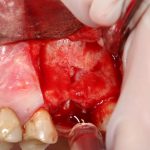

Подготовка костного ложа и фиксация аутотрансплантата

Возвращаемся к основной операционной области. Еще раз посмотрим на альвеолярный гребень, поофигеваем от его ширины и моих грандиозных планов:

Я зафиксировал костный блок практически без адаптации на несколько винтов. Обрати внимание, что винты находятся в зоне, где не планируется установка имплантатов. Фиксация должна быть надежной, поскольку мне еще предстояла подготовка лунок для имплантатов. Трех винтов для этого вполне достаточно.

Дальнейшая адаптация костного блока свелась к сглаживанию острых краев. После чего я приступил к подготовке лунок и установке имплантатов.